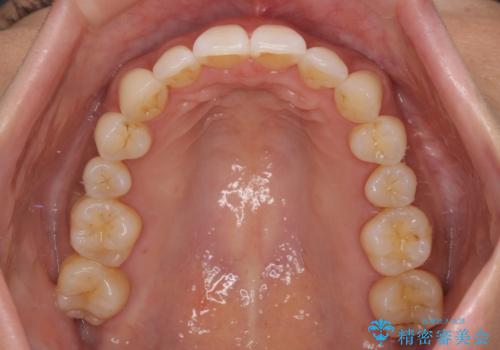

出っ歯になることなく、上下前歯が綺麗に接触する状態で仕上げることができました。